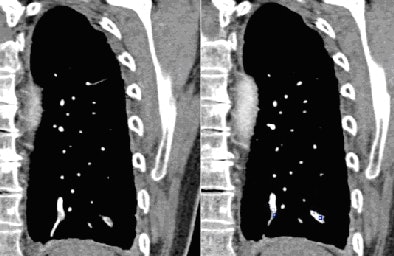

![]() |

| Notice both medial and lateral subsegmental PE (bottom right) found by CAD but missed by inexperienced readers. |